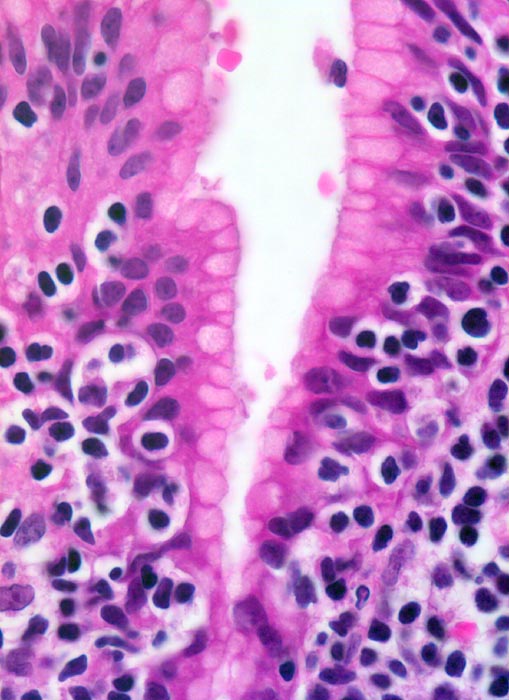

extranodales Marginalzonenlymphom vom MALT-Typ

Die Lymphomzellen infiltrieren das foveoläre Epithel.

73 jährige Patientin mit chronischer Helikobakter-Gastritis. Magenbefall ohne Lymphknotenbefall.

Die neoplastischen Zellen des MALT Lymphoms können unterschiedliche Differenzierungen zeigen (zentrozytoid, monozytoid, lymphozytoid oder plasmazellulär).

630